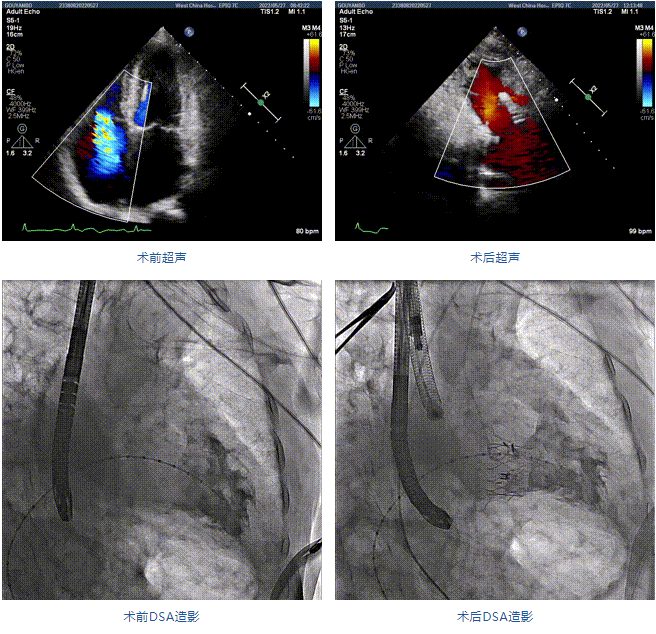

89歲男性。術(shù)前超聲報告顯示:雙房增大,左室壁肥厚,主、肺動脈增寬,三尖瓣重度反流。

團隊前期經(jīng)過多次討論,制定了周密的手術(shù)策略和預(yù)案。由于患者已是近九旬的超高齡老人,傳統(tǒng)外科開胸手術(shù)風(fēng)險極高,純介入經(jīng)血管三尖瓣替換能夠明顯減少創(chuàng)傷。術(shù)中陳茂及馮沅教授結(jié)合體表定位在造影指示下精準穿刺右側(cè)頸靜脈并預(yù)置兩把血管縫合器。成功建立經(jīng)皮血管入路后在食道超聲和DSA的引導(dǎo)下順利完成人工瓣膜植入,術(shù)后超聲和造影顯示人工三尖瓣同軸性良好,瓣架固定牢靠,無反流和瓣周漏,平均跨瓣壓差降為1mmHg。術(shù)畢收緊預(yù)置的血管縫合器縫線完成止血,縫合效果滿意,在手術(shù)室即刻拔除氣管插管。